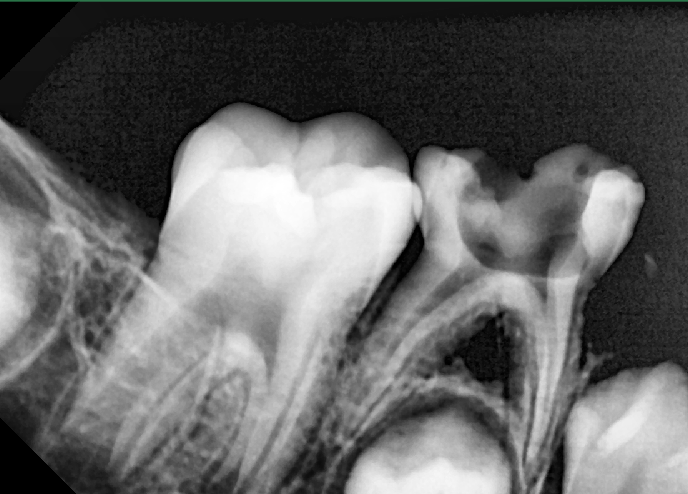

The RadioVisioGraphy (RVG) imaging system1 commonly used in dentistry to take intraoral periapical radiographs features the latest innovations in digital radiography, delivering the highest image resolution (> 20 LP/mm). RVG consists of a sensor, monitor, and microcomputer components

The RadioVisioGraphy (RVG) imaging system1 commonly used in dentistry to take intraoral periapical radiographs features the latest innovations in digital radiography, delivering the highest image resolution (> 20 LP/mm). RVG consists of a sensor, monitor, and microcomputer components .